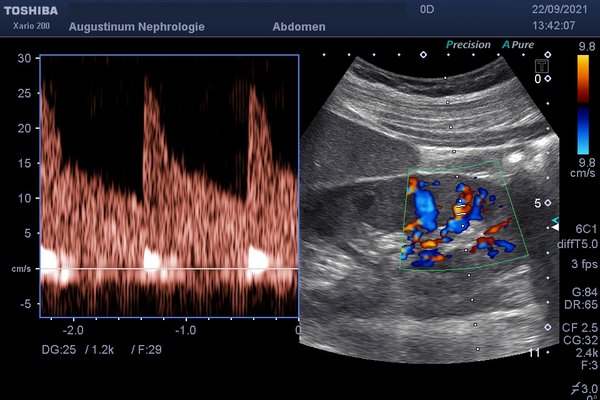

Bildgebung in der Nephrologie

Die Bildgebung nimmt in der Diagnostik von Nierenerkrankungen eine besondere Stellung ein. Hier steht am Anfang die Ultraschalluntersuchung mit Darstellung von Struktur, Durchblutung und Gefäßen der Nieren.

Die Ultraschalluntersuchung kann durch Kontrastmittel verbessert werden, welches im Wesentlichen aus kleinen Luftbläschen besteht und nicht schädlich für die Nieren ist.